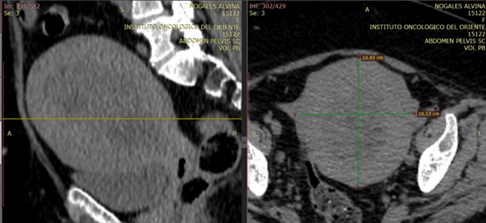

Se solicita una tomografía de control evidenciando útero aumentado en dimensiones (Imagen 1), múltiples adenopatías en cadena iliaca primitiva, iliaca externa bilateral y obturatriz izquierda, la de mayor dimensión de 18x 15 y la de menor tamaño 12x10mm. En los laboratorios de control se evidencia una anemia severa (Hb 6 g/dl Hto 19 %) por lo que se presenta a Comité de Tumores de Oncología Ginecológica decidiendo su Intervención quirúrgica más biopsia por congelación.